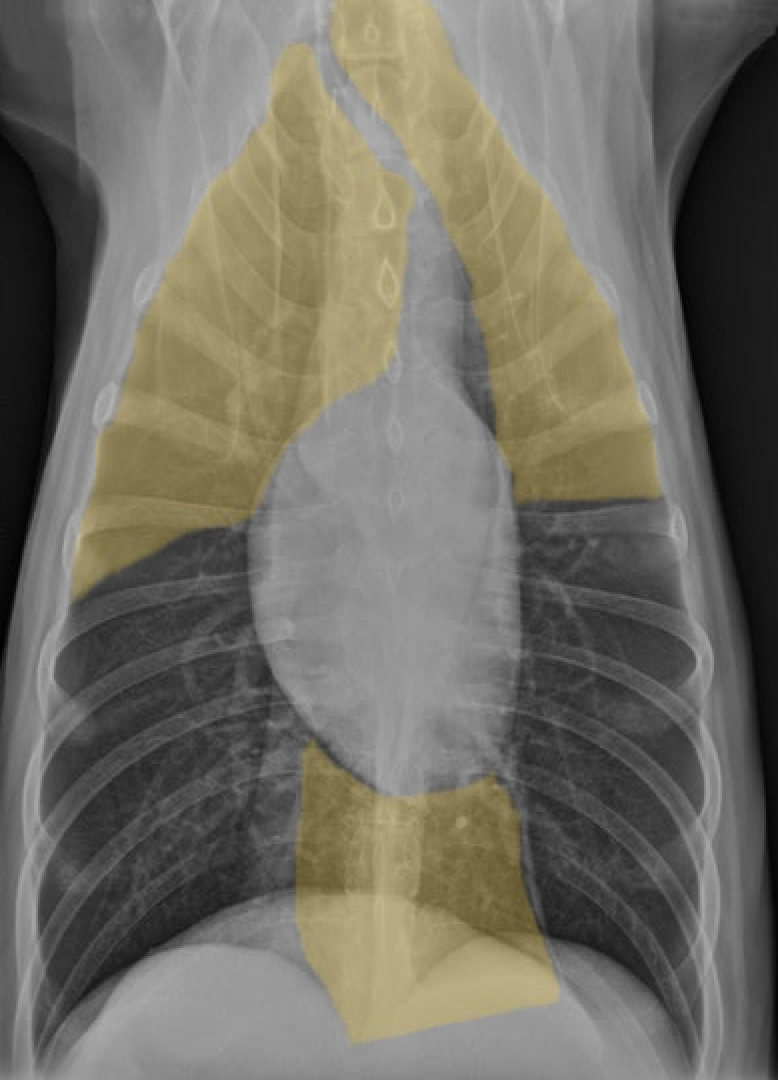

identify the structures

identify the pulomary arteries

identify the aorta

identify the ventral mediastiunum

identify the scapula

identify the ventral lung lobes